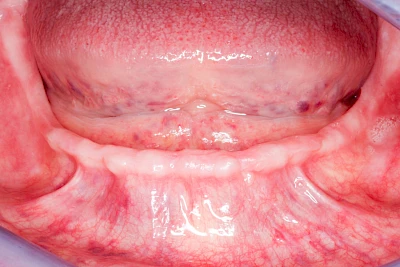

Knochenschwund (Atrophie)

Gehen die Zähne verloren, baut häufig auch der Kieferknochen ab (Knochenschwund). Die Geschwindigkeit und das Ausmaß des Knochenschwundes ist von vielen Faktoren abhängig. Neben der genetischen Veranlagung spielen auch Überbelastungen in Folge, z. B. bei ständigem Knirschen oder Pressen, eine Rolle. Auch wenn Zahnprothesen Tag und Nacht getragen werden, kann die ständige Belastung der Schleimhäute und des Knochens den Knochenschwund beschleunigen.

In seltenen Fällen schwindet nur der Knochen, aber nicht die bedeckenden Schleimhäute. In diesen Fällen spricht man von einem sogenannten "Schlotterkamm".